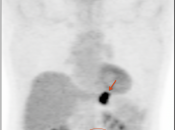

Recurrence & Restaging

• Restaging suspected recurrence.

• Distinguishing recurrence from post-therapeutic inflammation.

The difficulty with PET/CT imaging and gastric cancer is that it is both easy to overlook and easy to over-call.

Normal FDG uptake involving the stomach can be extremely variable. It is not uncommon to see diffuse intense uptake throughout the entire stomach or intense uptake limited to only a segment of the stomach (fundus, body or antrum).